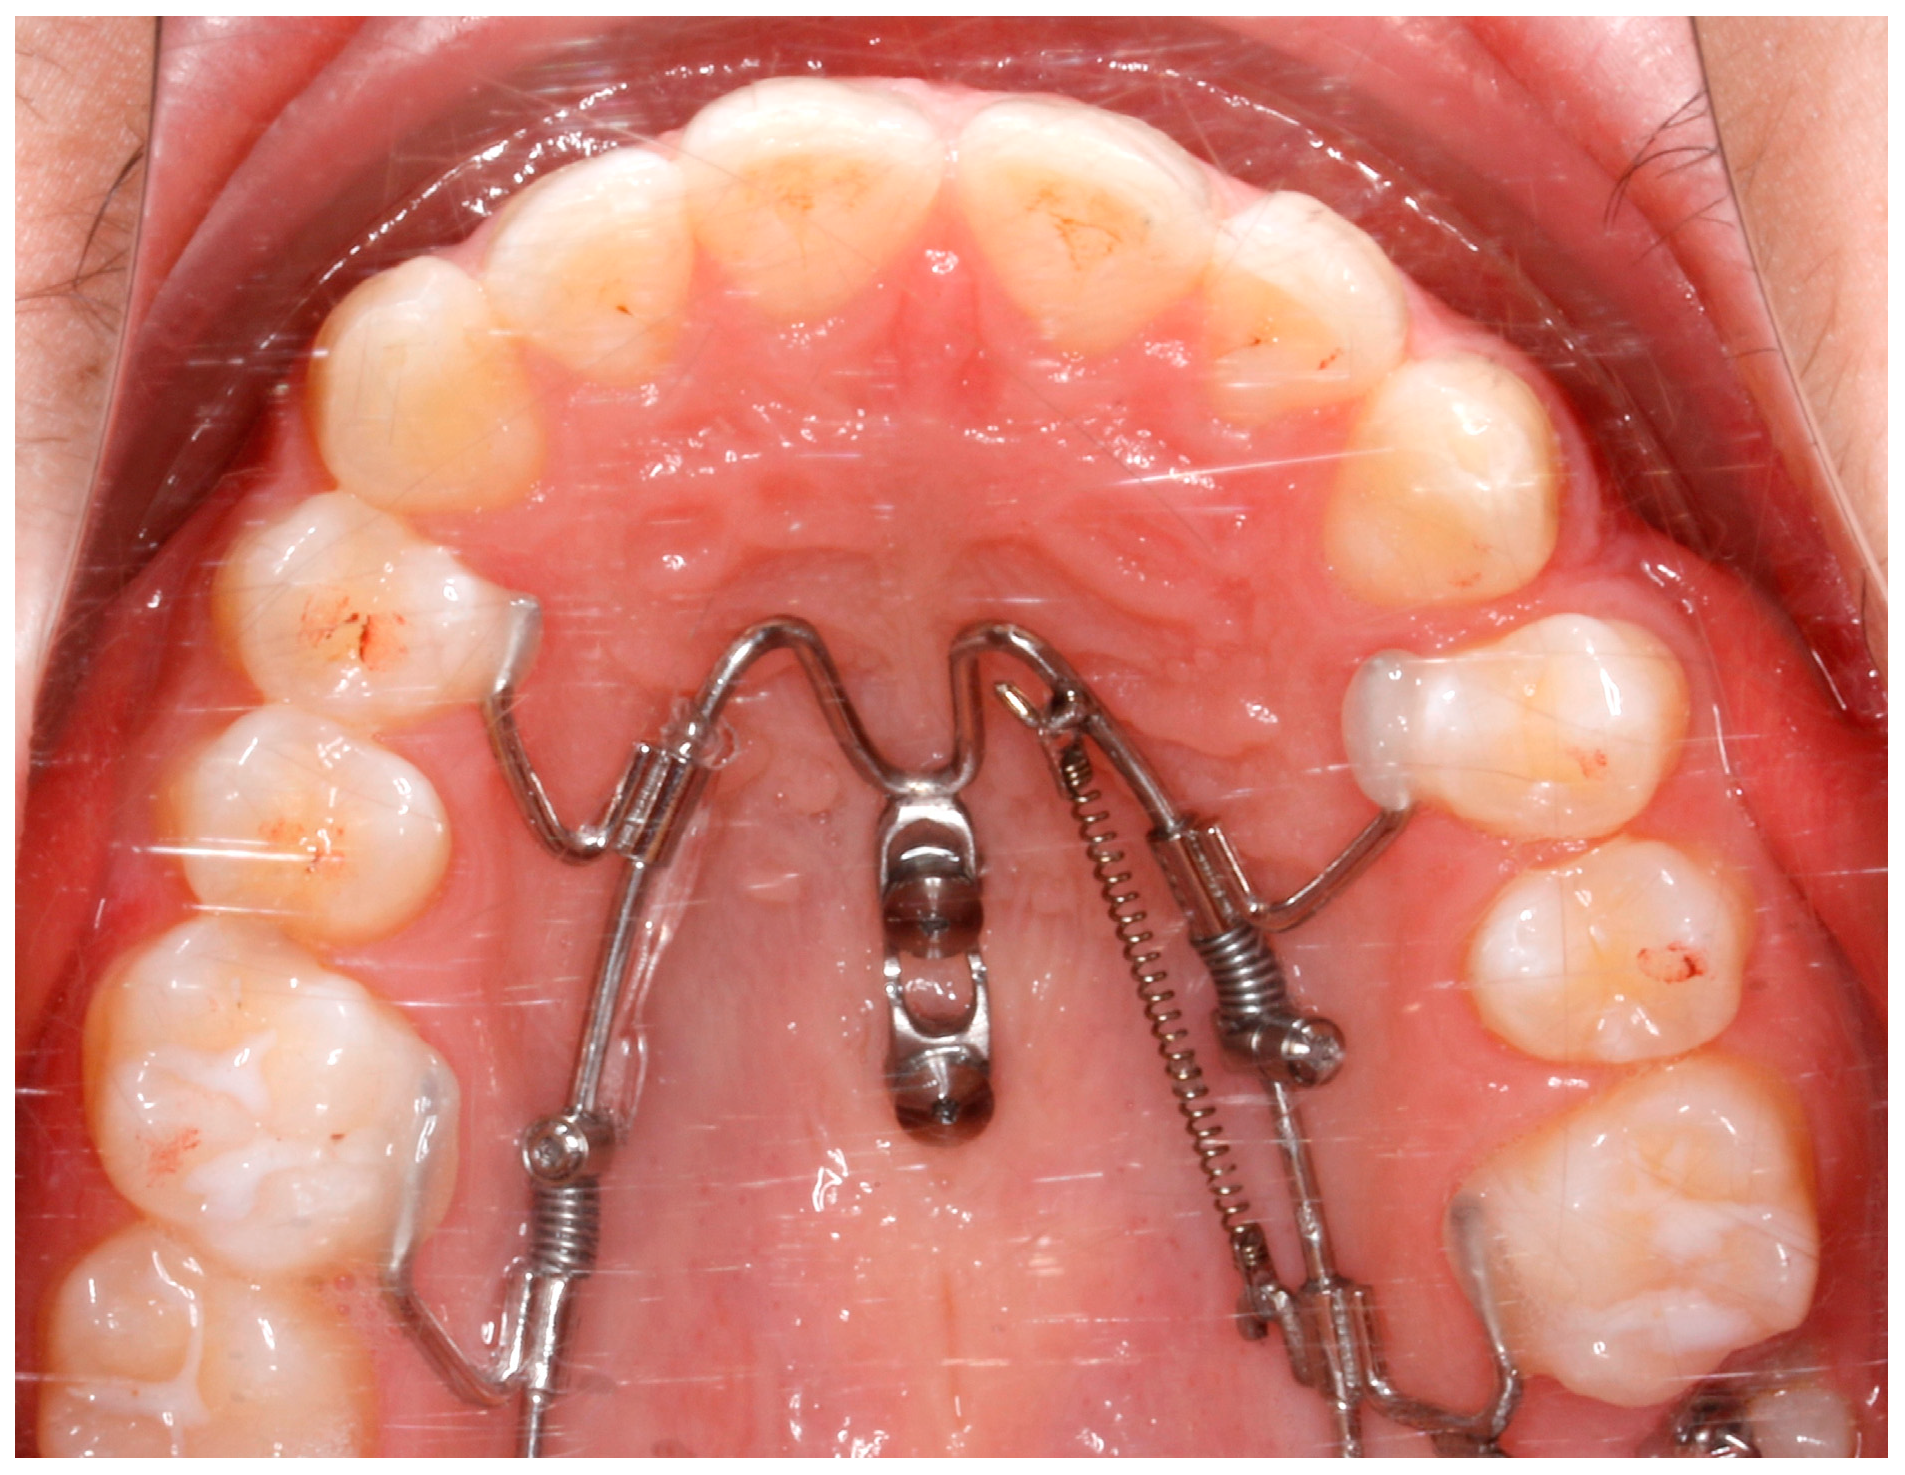

2.1. The Appliance

- Wilmes, B.; Nanda, R.; Nienkemper, M.; Ludwig, B.; Drescher, D. Correction of upper-arch asymmetries using the Mesial-Distalslider. J. Clin. Orthod. 2013, 47, 648–655. [Google Scholar] [PubMed]

- Wilmes, B.; Nienkemper, M.; Nanda, R.; Lübberink, G.; Drescher, D. Palatally anchored maxillary molar mesialization using the Mesialslider. J. Clin. Orthod. 2013, 47, 172–179. [Google Scholar] [PubMed]

- Wilhelmy, L.; Willmann, J.H.; Tarraf, N.E.; Wilmes, B.; Drescher, D. Maxillary space closure using a digital manufactured Mesialslider in a single appointment workflow. Korean J. Orthod. 2022, 52, 236–245. [Google Scholar] [CrossRef]